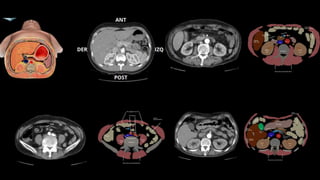

Los puntos más importantes son detectar el punto de transición, determinar la causa y

descartar la presencia de complicaciones.

Para facilitar la búsqueda del PT se emplean dos signos:

El “signo del pico”, dado que el punto de cambio de calibre simula un pico.

El “signo de las heces”, dado que debido a la obstrucción en el PT las heces se acumulan

proximalmente a este dando la típica imagen de patrón en miga de pan.